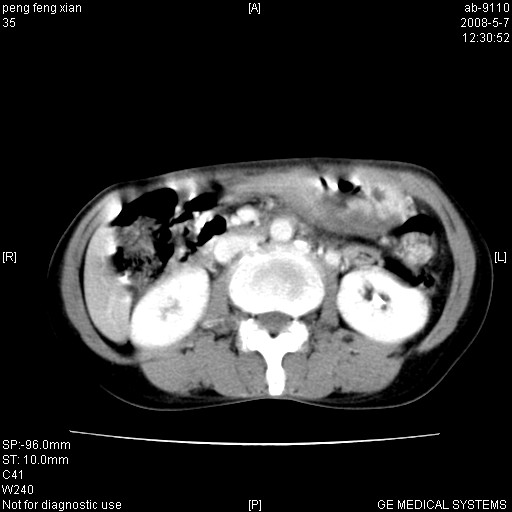

女,56岁。b超左一腹包块,考虑胃肠道肿瘤。

考虑为:胃肿瘤(胃癌?)。建议:行胃镜检查进一步明确诊断。

胃壁增厚,左前胸壁局限性隆起,考虑胃癌可能性大,建议做胃镜

典型胃癌胰体尾部受侵。

胃底占位待出;右肾结石?

胃体部胃壁增厚,不均匀性强化,与胰腺分解欠情.

考虑:胃癌,胰腺受侵待除外.

鉴别:胃淋巴瘤(强化不明显)

建议:胃镜检查.